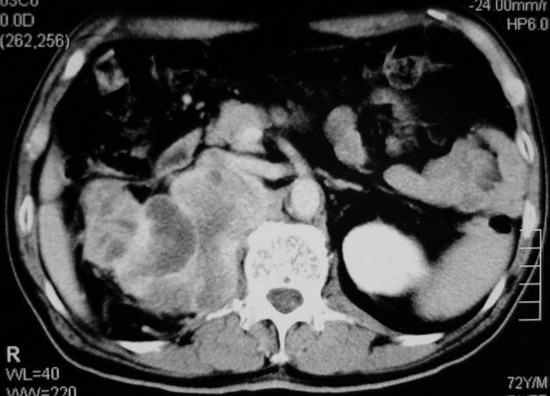

以下是引用杀毒软件在2008-11-17 19:15:00的发言:[br]考虑------右肾癌合并肾静脉---同侧肾上腺受侵可能性大

以下是引用zjzjr在2008-11-17 20:45:00的发言:[br]考虑------右肾癌合并肾静脉---同侧肾上腺受侵可能性大及腹膜后淋巴结转移.